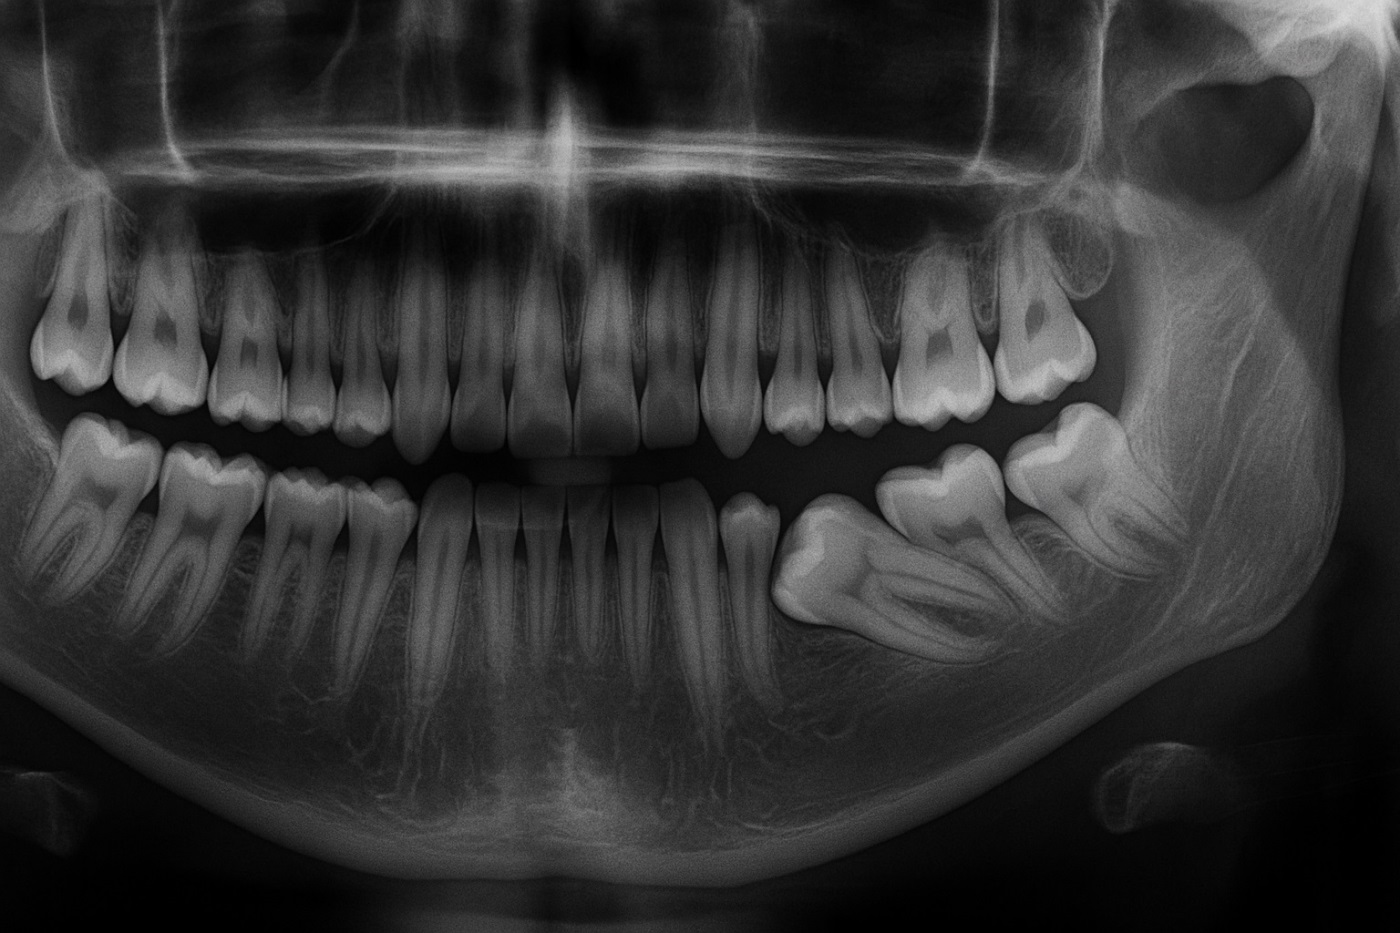

Прицельный снимок или компьютерная томография обязательный этап. Они позволяют врачу увидеть то, что скрыто под десной: количество, форму и расположение корней, кисты и гранулемы, близость к важным анатомическим структурам, например, к гайморовой пазухе или нижнечелюстному нерву. На основе этих данных хирург составляет план удаления.

Во-первых, они часто бывают ретинированными, скрыты в кости, или дистопированными, растут под наклоном, что сразу переводит их удаление в категорию сложных.

Во-вторых, их корни могут быть сильно изогнуты и располагаться близко к нижнечелюстному нерву, что требует от хирурга особой точности и предварительной диагностики с помощью КТ.